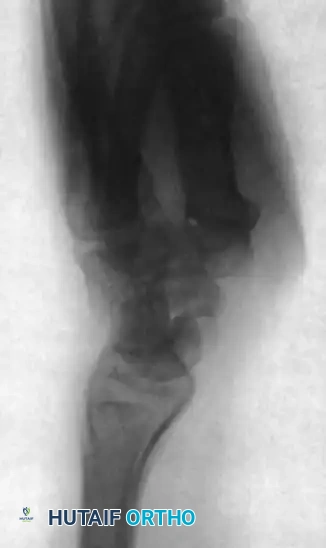

FIGURE 69-42 A: Lateral radiograph of the wrist with a scaphoid nonunion and humpback deformity. Note the severe lunate extension secondary to carpal collapse.